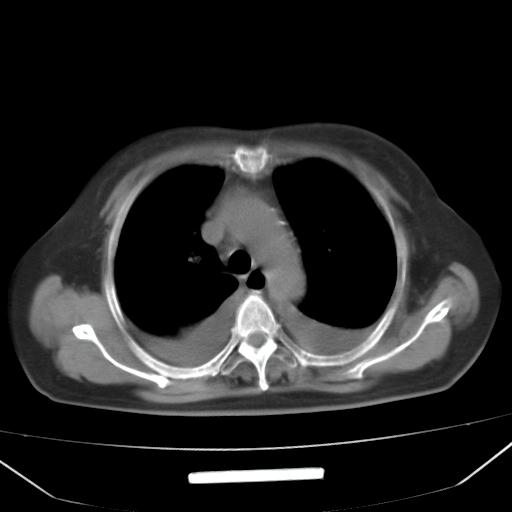

以下是引用liuyue在2008-4-19 22:25:00的发言:[br]先考虑:1.心衰伴肺水肿、双侧胸腔积液、叶间积液、双下肺不完全性肺不张; [br] 2.冠状动脉粥样硬化。

以下是引用lijuanln在2008-4-19 23:05:00的发言:[br]两侧胸腔积液,肺水肿[br]心包积液[br]提示心衰

以下是引用jiangjing在2008-4-20 10:43:00的发言:[br]结合病史支持 冠心病[冠状动脉钙化],心功能不全,肺淤血、肺水肿,双侧胸腔与斜裂积液